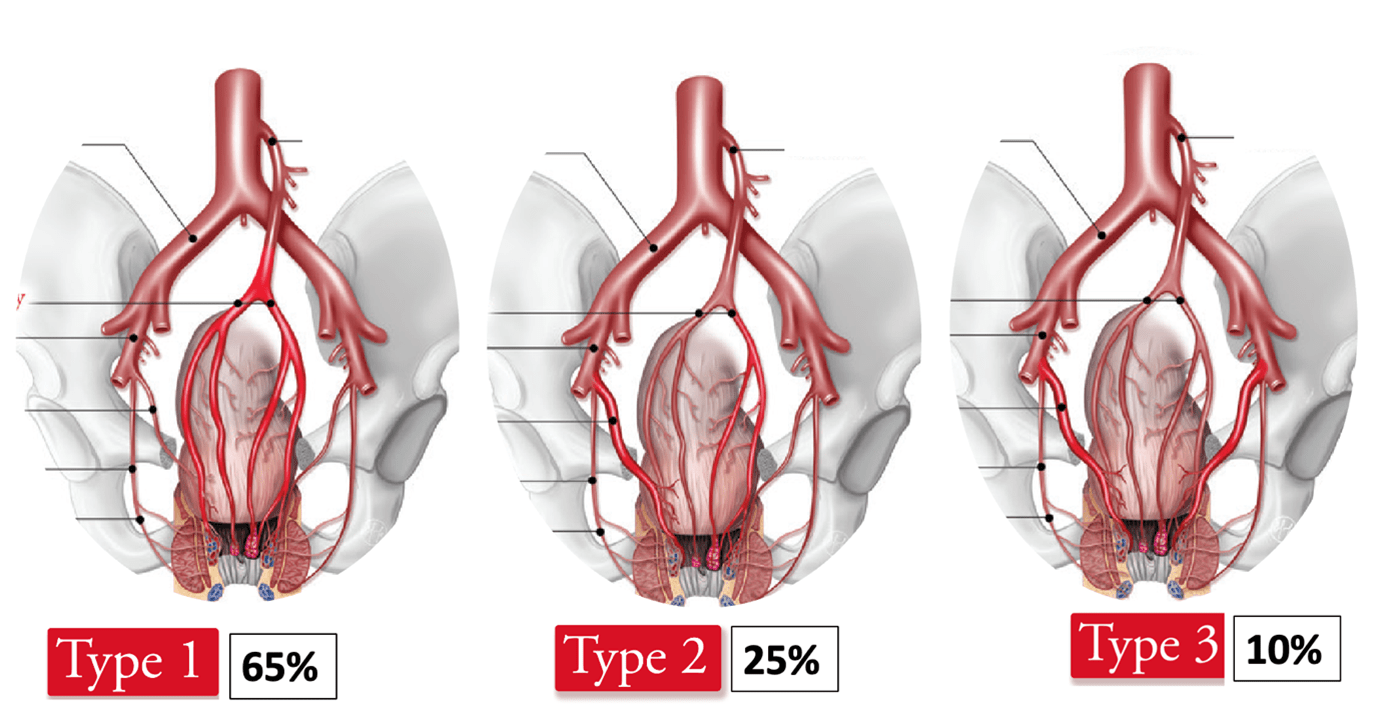

Over the past 15 years, the growing interest of interventional radiology in hemorrhoidal embolization has led to a better understanding of hemorrhoidal vascularization and its anatomical variations. Based on recent anatomical and angiographic observations, a new classification of hemorrhoidal arterial supply has been proposed, consisting of three main vascular patterns that can directly influence the embolization strategy (5).

These anatomical variations involve the middle rectal arteries (MRAs) in approximately one-third of cases. A detailed understanding of the arterial anatomy of hemorrhoidal vascularization is therefore essential, as it allows the operator to anticipate potential variants and adapt the embolization technique during the procedure.

Figure 1. Anatomical classification of arterial supply of hemorrhoids. https://doi.org/10.1148/rg.220014